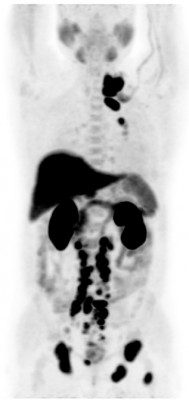

| Норма | Метастазы рака предстательной железы | Метастазы рака предстательной железы |